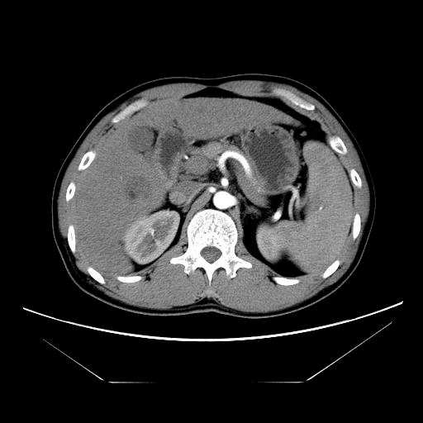

Multi-phase computed tomography (CT) images provide crucial complementary information for accurate liver tumor segmentation (LiTS). State-of-the-art multi-phase LiTS methods usually fused cross-phase features through phase-weighted summation or channel-attention based concatenation. However, these methods ignored the spatial (pixel-wise) relationships between different phases, hence leading to insufficient feature integration. In addition, the performance of existing methods remains subject to the uncertainty in segmentation, which is particularly acute in tumor boundary regions. In this work, we propose a novel LiTS method to adequately aggregate multi-phase information and refine uncertain region segmentation. To this end, we introduce a spatial aggregation module (SAM), which encourages per-pixel interactions between different phases, to make full use of cross-phase information. Moreover, we devise an uncertain region inpainting module (URIM) to refine uncertain pixels using neighboring discriminative features. Experiments on an in-house multi-phase CT dataset of focal liver lesions (MPCT-FLLs) demonstrate that our method achieves promising liver tumor segmentation and outperforms state-of-the-arts.